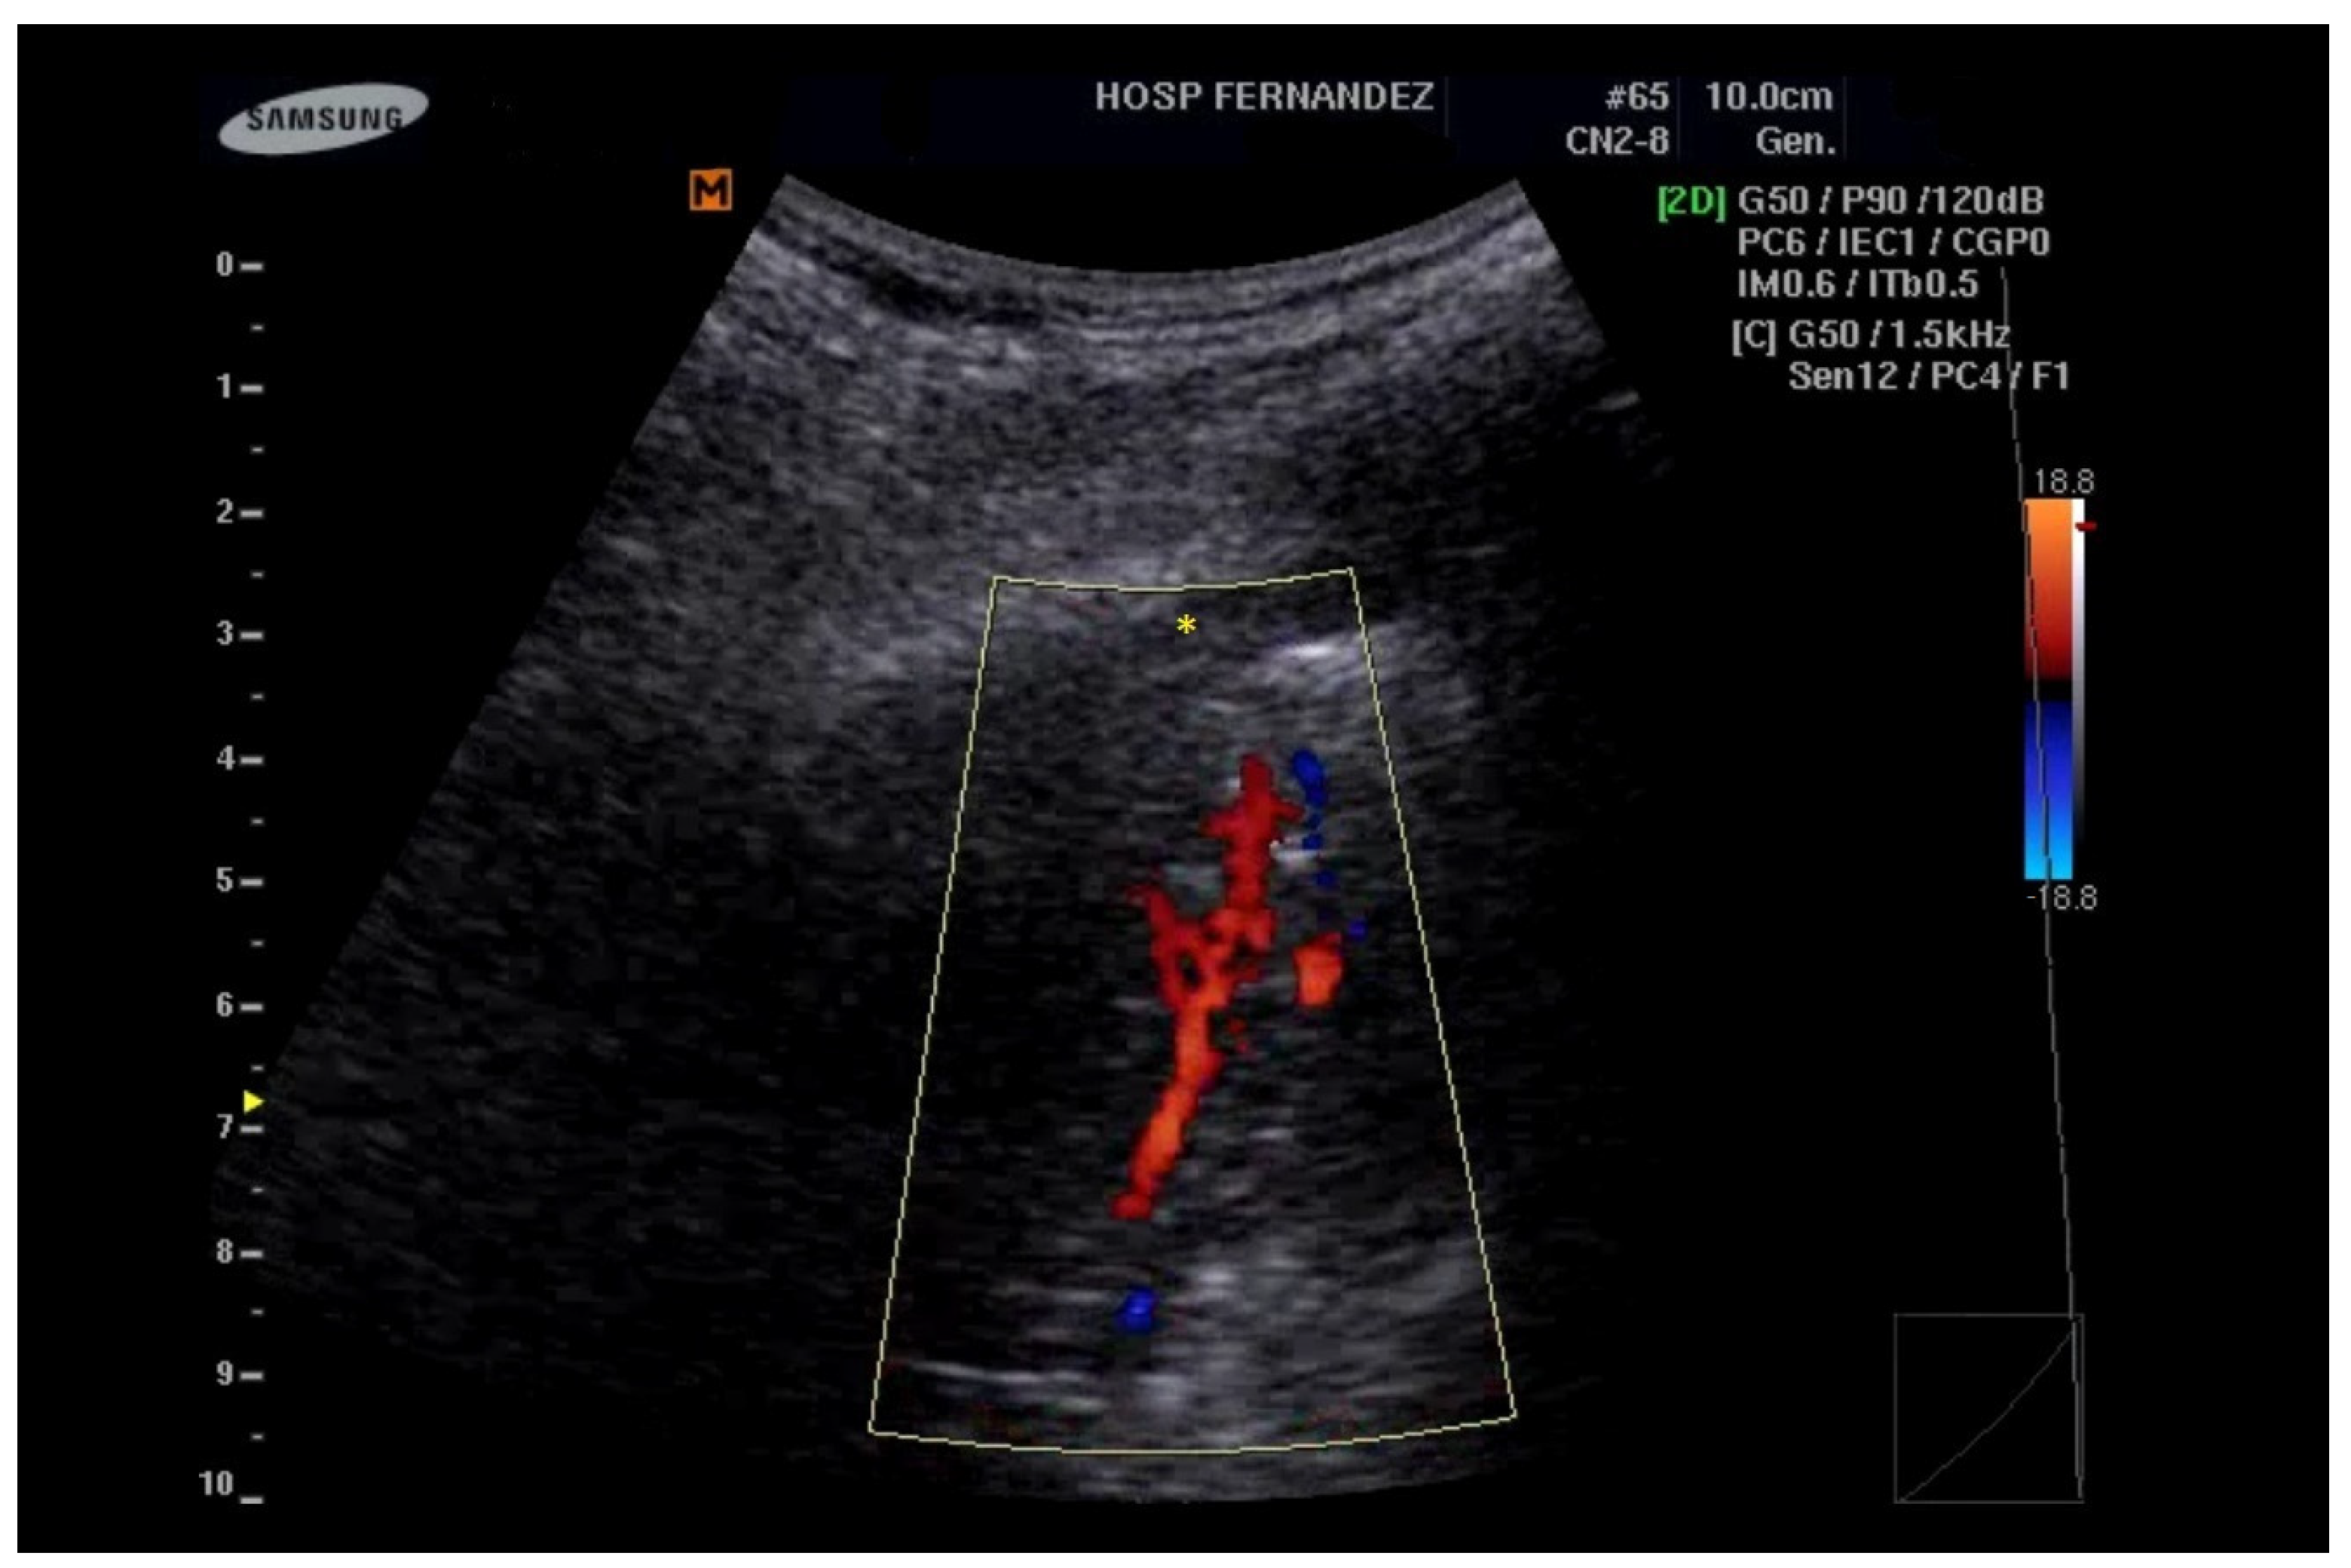

- Görg, C.; Bert, T. Transcutaneous colour Doppler sonography of lung consolidations: Review and pictorial essay. Part 1: Pathophysiologic and colour Doppler sonographic basics of pulmonary vascularity. Ultraschall Med. 2004, 25, 221–226. [Google Scholar] [CrossRef]

- Görg, C.; Bert, T. Transcutaneous colour Doppler sonography of lung consolidations: Review and pictorial essay. Part 2: Colour Doppler sonographic patterns of pulmonary consolidations. Ultraschall Med. 2004, 25, 285–291. [Google Scholar] [CrossRef] [PubMed]

| Pneumonia | NO | YES, if present | YES | NO | NO | YES | YES | YES |

| ARDS | NO | YES | YES | YES | YES | YES | YES (conditional to severity) | YES (conditional to the severity) |